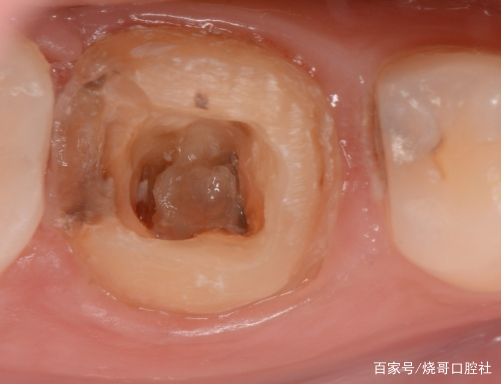

1、口腔鏡檢查:通過口腔鏡檢查,可以清晰地觀察到牙齒表面的牙洞以及牙洞內的情況,醫(yī)生可以判斷牙洞是否已深入牙髓,并評估病情嚴重程度。

2、探診檢查:使用牙科探針檢查牙洞周圍組織的健康狀況,了解牙洞深度及與牙髓的關系。